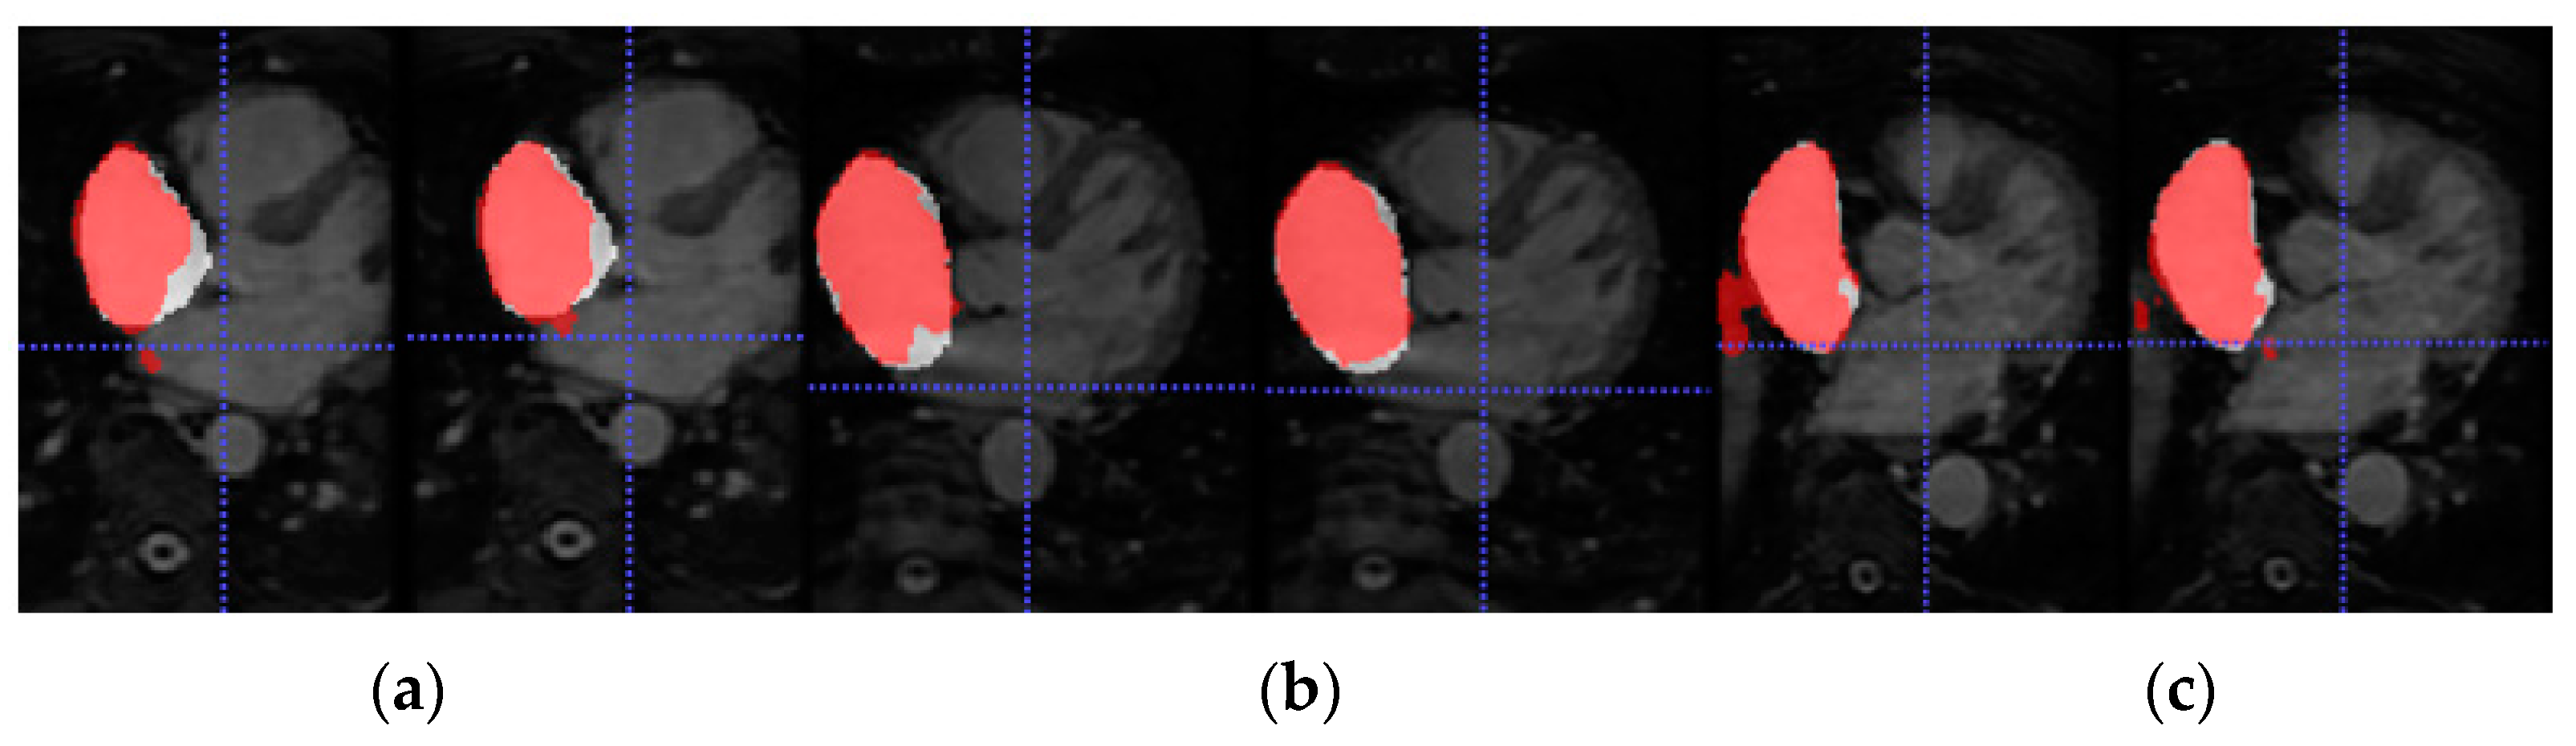

4.2. Source Domain Model

Firstly, the dual 3D U-Net was trained and tested with a large number of labelled images from LGE-MRI (source) domain. For this, Database 1 was employed which contains 100 volumes each of them composed of 88 slices. The aim of this experiment was to pre-train the network and obtain a high-performance model from which knowledge can be inferred. The mean Dice coefficient and standard deviation obtained during evaluation across the 20 testing volumes were 0.9155 ± 0.0270. The segmentation results for three representative patients and slices of Database 1 can be observed in Figure 4.

Figure 5 shows the axial view of predictions obtained for three representative patients (and slices) of the testing cohort from Database 3 with the different trained models for LA segmentation.

In this section, we review the results obtained in the different experiments presented in Section 4. Firstly, the source network was trained with a large number of annotated LGE-MRI samples (Database 1). As can be observed, the model achieved very high accuracy segmentation results. This is expected as Database 1 corresponds to the data provided by the 2018 LA segmentation challenge [25], and the network proposed by [14] was specifically designed to face this challenge. Therefore, by keeping the same learning parameters, the Dice obtained coincides with the Dice reported in [14] (0.91–0.92). The segmentation masks shown in Figure 5 further highlight the high-accuracy performance of this model.

Figure 4. Axial slices of LA segmentations for three representative patients (ac) obtained through the LGE-MRI source model. Ground-truth mask in white, prediction mask in red and intersection in pink.

Figure 5. From top to bottom, axial slice of LA segmentations for three patients obtained through models (a) LGE-MRI, (b) w/o SDA and (c) w-SDA. Ground-truth mask in white, prediction mask in red and intersection in pink.